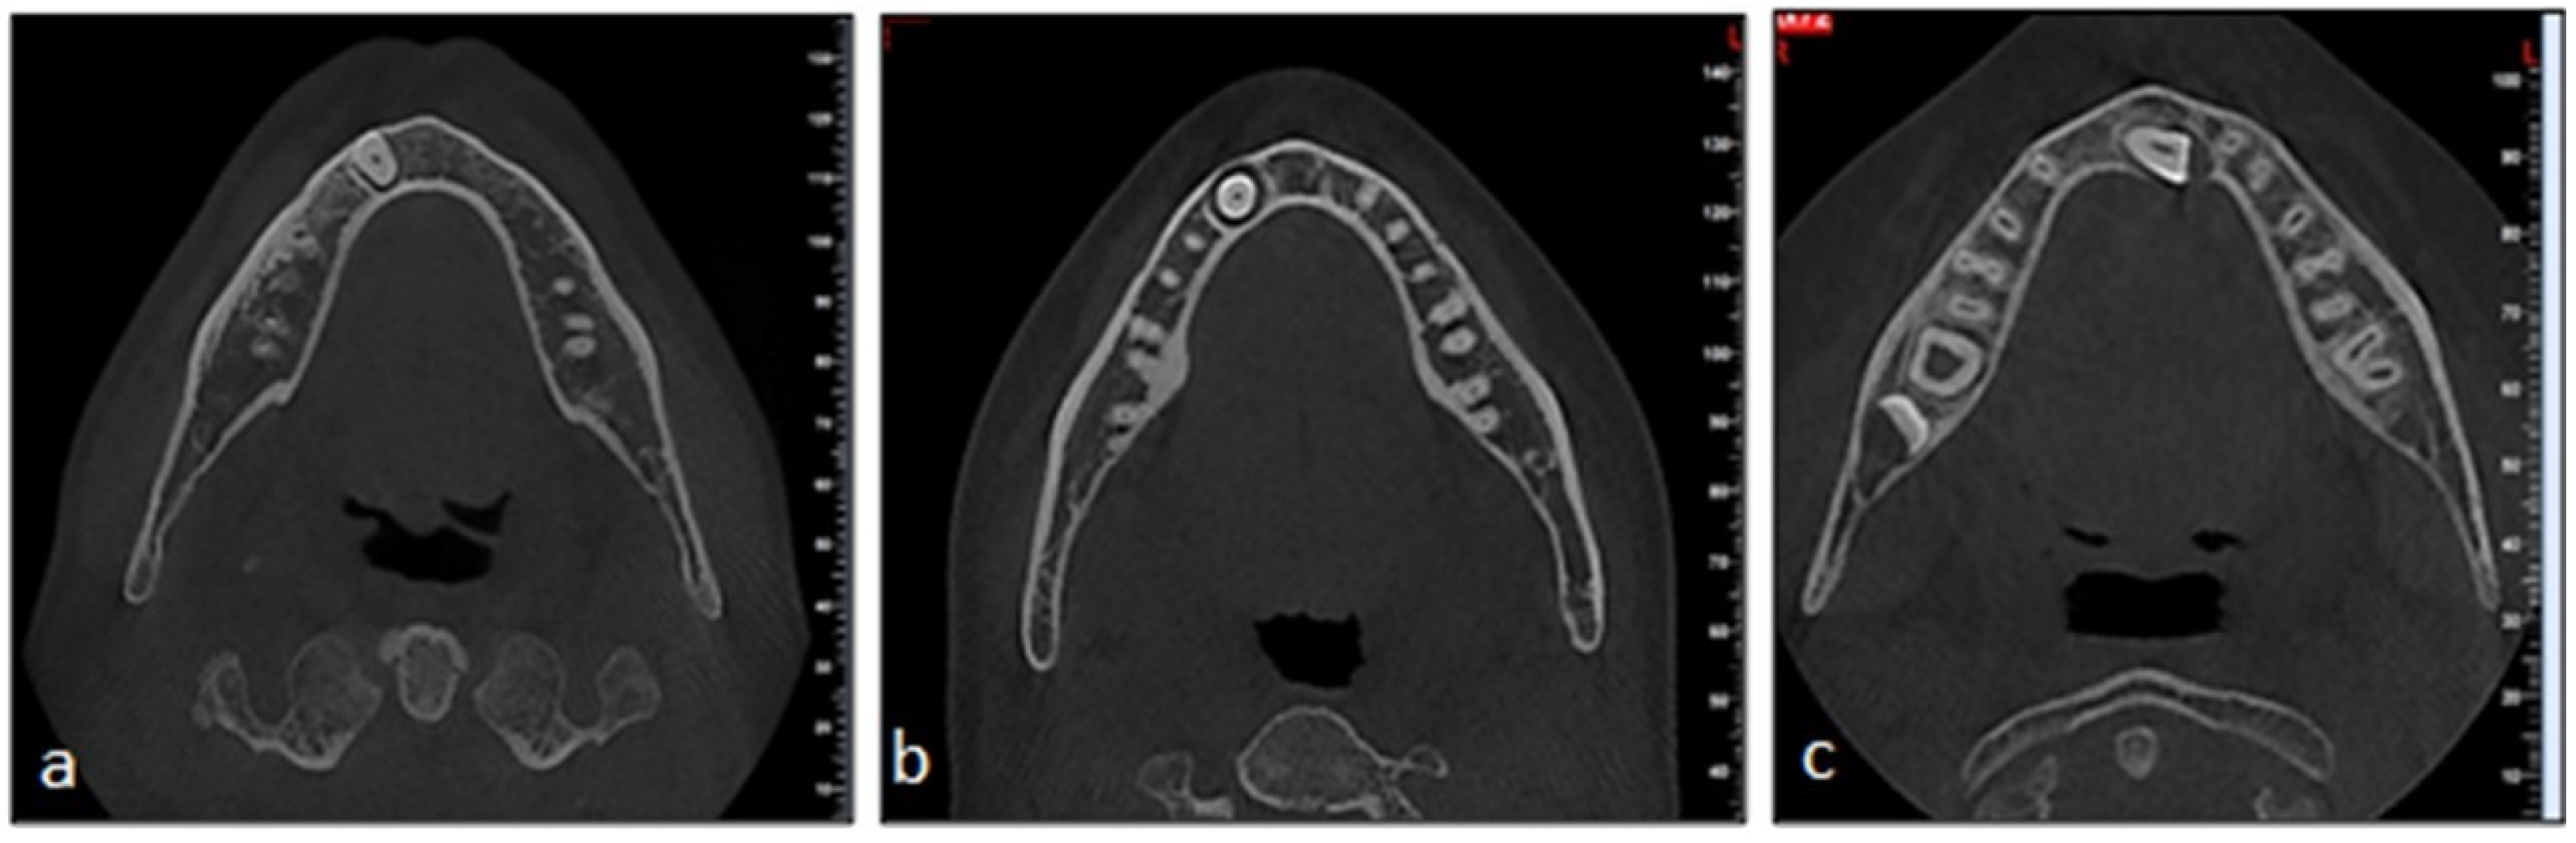

2. Materials and Methods